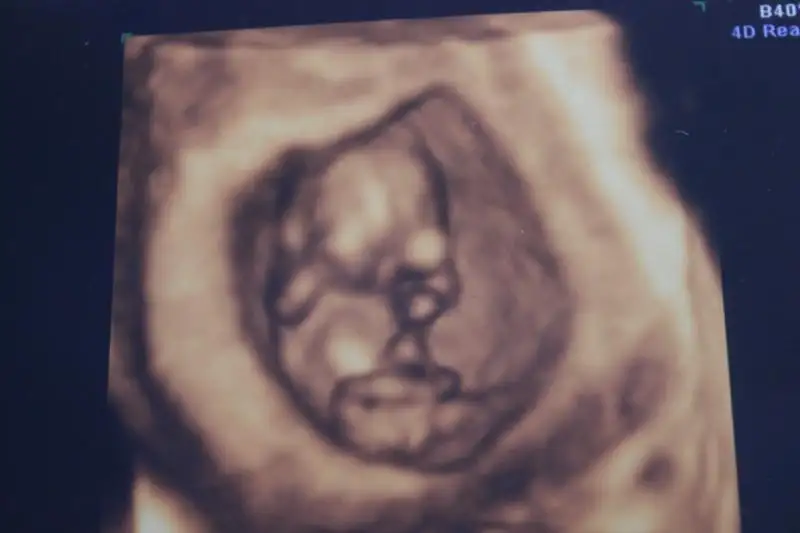

ya kızlar benim iki hafata önceki ultrasonum var belli midir? dr erkek muhtemelen dedi ama kesin demedi. yeni ultrasonu ekleyemedim bir türlü ışık patlaması oluyor. çocuğun kafası kocaman görüyodu korktum ya siiznkilerde de öyle oldu mu? kötü bişey olsa dr söylerdi dimi? ya da ultrasn eski diye mi öyle çıktı?

Eki Görüntüle 1047942

Eki Görüntüle 1047943